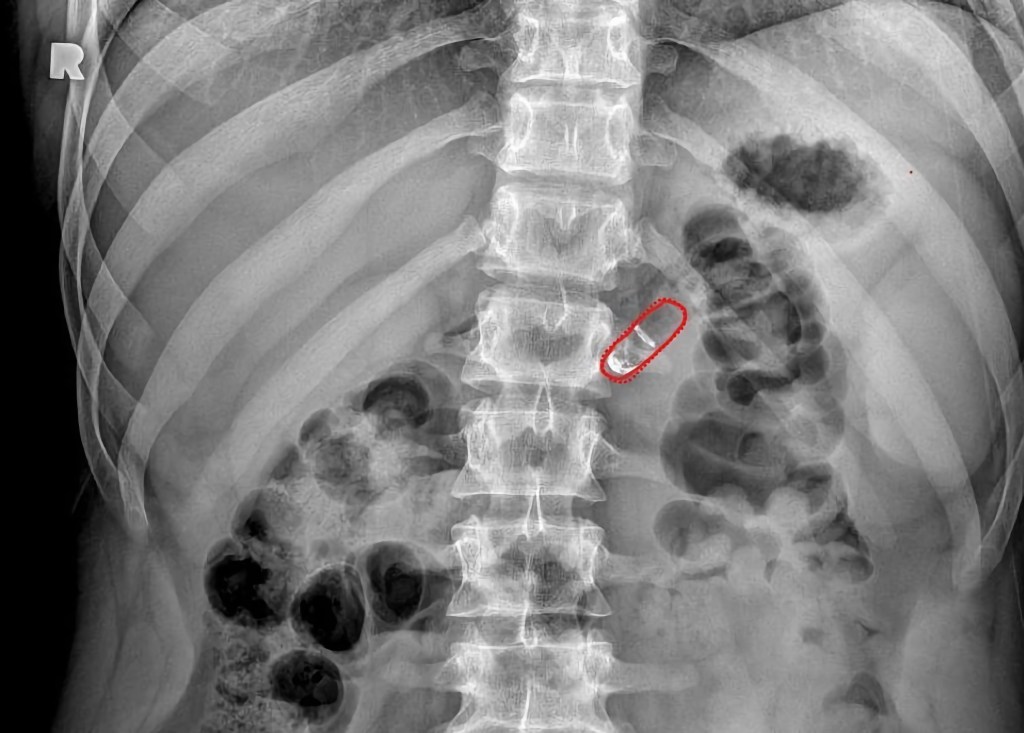

Image Credits:Rani Therapeutics

Rani Therapeutics’ approach is based on inherent properties of the gastrointestinal tract. An injecting mechanism in their pill is surrounded by a pH-sensitive coating that dissolves as the capsule moves from a patient’s stomach to the small intestine. This helps ensure that the pill starts injecting the medicine in the right place at the right time. Once there, the reactants mix and produce carbon dioxide, which in turn inflates a small balloon that helps create a pressure difference to help inject the drug-loaded needles into the intestinal wall. “So it’s a really well-timed cascade of events that results in the delivery of this needle,” said Imran.

Despite its somewhat mechanical procedure, the pill itself contains no metal or springs, reducing the chance of an inflammatory response in the body. The needles and other components are instead made of injectable-grade polymers, that Imran said has been used in other medical devices as well. Delivering the injections to the upper part of the small intestine also carries little risk of infection, as the prevalence of stomach acid and bile from the liver prevent bacteria from readily growing there.